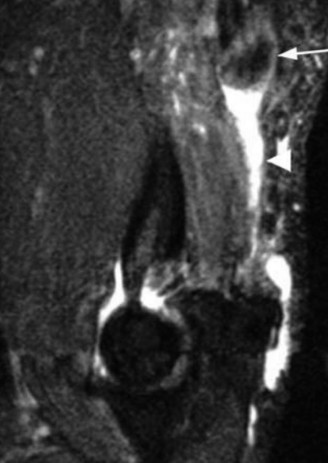

The answer is (B). As the four layers of the lateral rotator interval insert onto the lesser tuberosity of the humerus, they form the “reflection pulley” that forms a sling around the tendon of the long head of the biceps before it enters the bicipital (intertubercular) groove. A tear of the upper part of the subscapularis can disrupt this reflection pulley and destabilize the biceps tendon, allowing it to sublux or even

dislocate out of its groove, usually in a medial direction. If this happens, the intertubercular groove will be empty on MRI. Often, a “pulley sign” will also be seen on MRI when this occurs. This is when contrast material extravasates extra-articularly just over the superior border of the subscapularis tendon on axial images (see Fig. 2–11).

Figure 2–11_Axial T1 MRI. Left: an empty intertubercular sulcus, positive pulley sign (straight _black arrow on left), and dislocated biceps tendon (curved black arrow). Right: fraying subscapularis tendon (arrow). (From Lyons RP, Green A. Subscapularis tendon tears. J Am Acad Orthop Surg. 2005;13(5):353–363.)